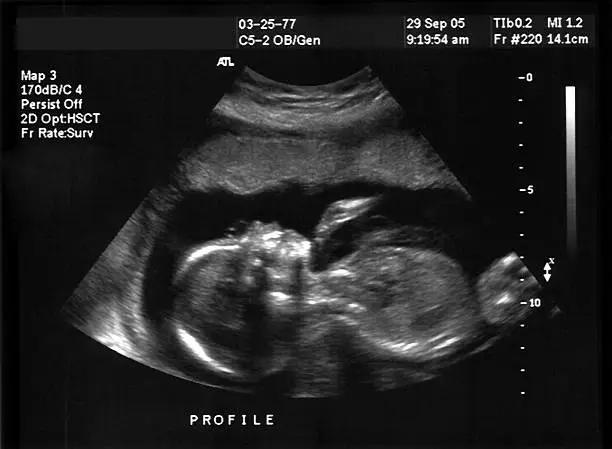

착상혈은 임신 초기, 즉 수정이 이루어진 후 대략 6일에서 12일 사이에 발생할 수 있습니다. 이는 배아가 자궁벽에 성공적으로 자리 잡았을 때 일어나는 현상으로, 수정란이 이동하여 자궁 내막에 부착되면서 내막의 작은 혈관들이 손상되어 출혈이 일어날 수 있습니다. 대개 배란 후 약 일주일에서 열흘 정도가 지난 시점에 착상혈이 발생하므로, 이는 예상 생리일과 겹칠 수 있어 생리와 혼동될 수 있습니다.

임신 초기에는 착상혈 외에도 다양한 신체적 변화가 동반될 수 있습니다. 여성의 몸은 수정 후 호르몬 변화에 민감하게 반응하며, 이는 다양한 형태의 신체적 변화를 유발합니다. 특히 임신 초기에는 프로게스테론이라는 호르몬의 급격한 증가로 인해 체온이 상승하거나 가슴이 민감해질 수 있습니다. 또한 피로감이 쉽게 느껴지며, 소화 불량이나 메스꺼움, 심지어 구토까지도 임신 초기 증상으로 나타날 수 있습니다.